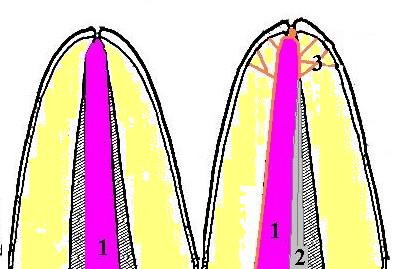

Técnica de condensación lateral

Esta técnica es la más utilizada por odontólogos y

especialistas.

Se realiza con un cemento sellador y conos de gutapercha. Se

ubica un cono de gutapercha acorde al diámetro del instrumento

que ha mecanizado la zona apical, en este caso fue una lima Nº

25. Ver imagen derecha (1)

El cono maestro Nº 25 se embadurna con el cemento sellador y

se lo hace llegar hasta el fondo del ápice, luego con un

espaciador digital Nº 25 se presiona hacia el fondo y contra las

paredes del conducto (2), con esto se logra una

condensación lateral para que el cemento sellador penetre el

delta apical y conductos accesorios (3)

Mientras se genera espacio con el condensador digital Nº 25,

se adicionas mas conos accesorios del 25, hasta obturar el

conducto radicular en su totalidad.

El mayor volumen de obturación está determinado por los conos

de gutapercha, mientras el cemento sellador queda limitado como

obturador de los conductos accesorios y túbulos dentinarios.

(1,2,27)

Técnica del cono único y

condensación vertical

Los fabricantes de conos de

gutapercha producen conos con conicidades especiales (taper) que

coincide con la última lima mecanizada de tratamiento.

-

La técnica en si consiste

en poner el cemento sellador en el tercio apical del cono.

-

lleve el cono con el

cemento sellador a la preparación, hasta hacer tope,

-

corte el exceso del cono

con una espátula calentada en el mechero

-

luego con un condensador

calentado con el mechero, del mismo diámetro que el cono, realice una presión vertical

moderada para que el cono encaje en toda la longitud de

trabajo del conducto; y el cemento refluye por los canales

accesorios. Ver imagen derecha.